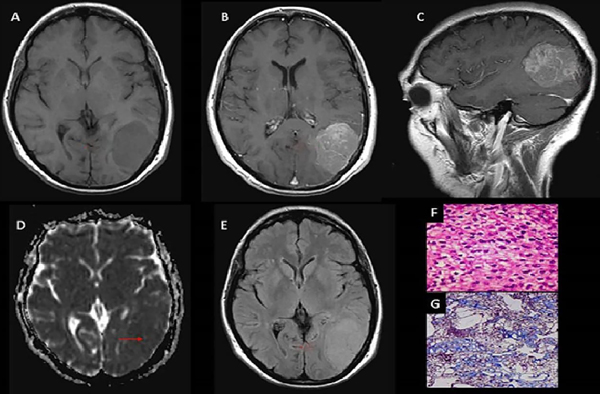

Figura 2. Meningioma de células claras, grado II OMS. (A) RM T1 axial: Meningioma parietooccipital izquierdo que produce efecto de masa (flecha). (B y C) T1 axial y sagital con Gd: Realce tenue heterogéneo (flechas). (D) Mapa de ADC: Comportamiento isointenso con aislados sectores de aumento de intensidad (flecha). (E) RM Flair axial: Efecto de masa, sin edema vasogénico (flecha). (F y G) Microscopía: Proliferación meningocelular con sectores de hipercelularidad y aumento de la tasa núcleo-citoplasma, con presencia de necrosis tumoral multifocal y sectores de atipia nuclear con nucléolos y 5 mitosis por 10 campos de aumento.